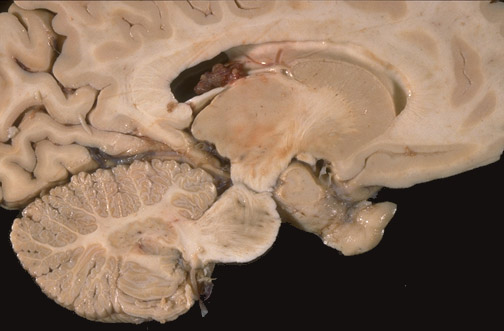

Identify the following regions of the normal brain in the image above: Thalamus - Pons - Descending Corticospinal and Corticobulbar Tracts - Dentate Nucleus - Caudate Nucleus - Optic Chiasm - Choroid Plexus - Fornix